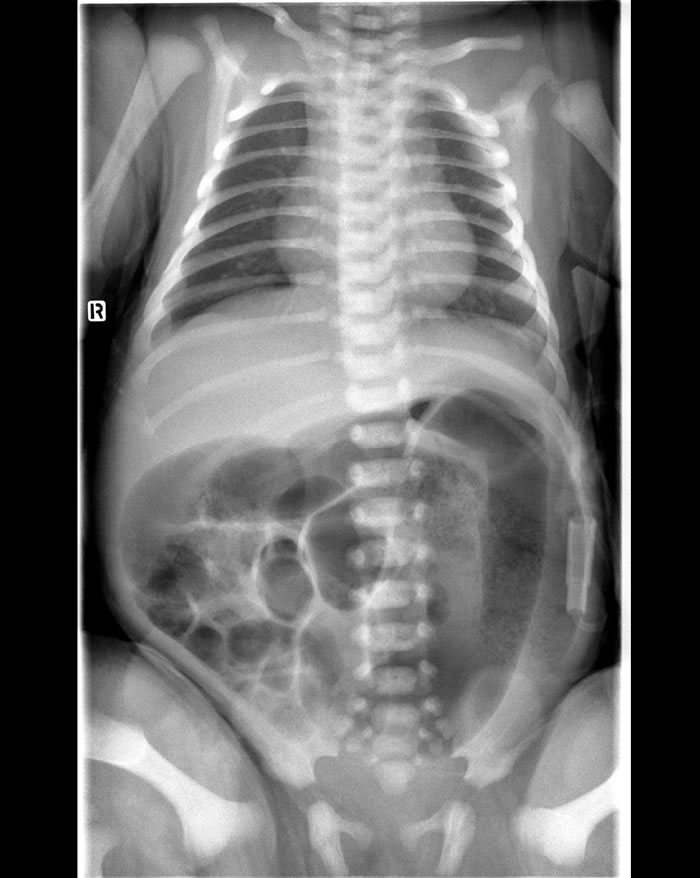

- rx addome in posizione eretta (fig.2), che dimostra anse intestinali marcatamente distese, senza evidenza di gas a livello rettale.